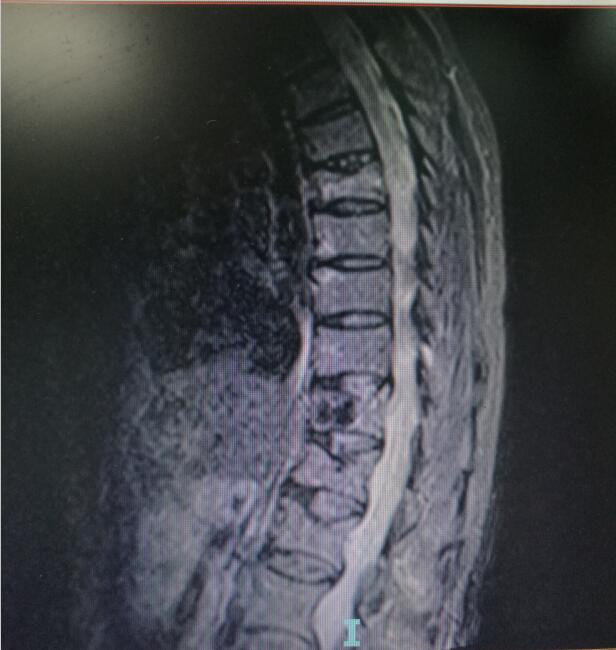

术前MRI(核磁共振检查

“经骨二科收治入院,完善相关检查后,明确诊断为老年性骨质疏松性胸腰椎压缩骨折,这是发生在老年人身上的一个常见病,科室对此类病例具有成熟的治疗经验。” 据泸州市中医医院骨伤二科副主任中医师唐国皓介绍,医护人员经过与患者耐心沟通,迅速确定了手术治疗方案。

入院后第四天,由骨伤二科副主任杨陈一、刘永森医生、唐国皓医生联合为患者成功实施了微创下的经皮穿刺椎体后凸成形术。术后,患者腰背部疼痛逐渐缓解,术后第二天即下床活动。